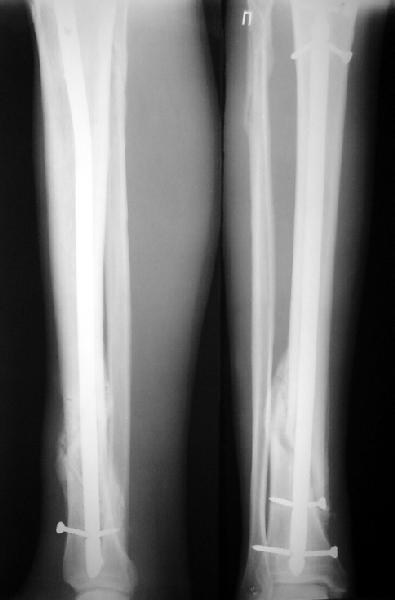

Ok. А также и следующий, в 3 месяца.

Это наглядная демонстрация возможности ранней полной нагрузки при нестабильном по оси повреждении, причем не в самых благоприятных механических условиях - при плохом сопоставлении, со слабым фиксатором.

JOM> Ваш больной имеет счастье, что первым согнулся проксимальный

JOM> замыкающий винт, а не дистальный и гвоздь не пенетрировал

Это не счастье, а тонкий инженерный расчет ;-))

Сверху - один статический винт, а снизу - три. Что раньше сломается? Конечно, он потом и нижние сломал, и Вы правы, если бы верхний динамичесий винт уже уперся бы в нижний край отверстия, будь гвоздь подлинее, перфорировал бы сустав как пить дать.

Как я уже говорил, мы сделали выводы из этого и других подобных случаев. Очевидно, решений проблемы два - либо уменьшить нагрузку, либо увеличить прочность фиксатора. Первое решение работает не со всеми больными, так что пошли по второму пути - мы больше не используем гвозди с запирающими винтами диаметром 4 мм.